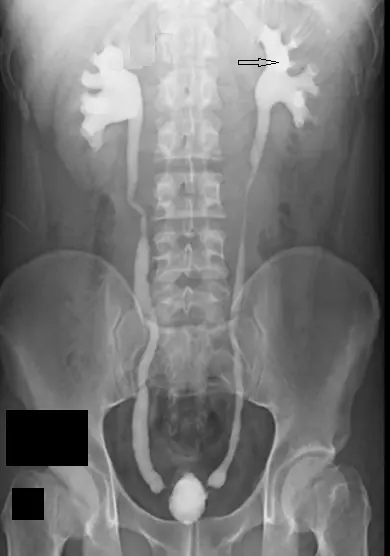

腎盂攝影( pyelography )影像如下圖所示,箭頭所指的構造是:

- 影像呈現:這是一張對比劑顯影下的泌尿道攝影影像(呈現雙側腎臟集尿系統、輸尿管至膀胱的顯影,屬於典型的 IVP 影像)。

- 解剖特徵對應:

- 顯影劑最外側呈現杯狀(cup-like)或半月形凹陷的構造為小腎盞(minor calyx),其凹陷處即為腎乳頭(renal papilla)所在位置。

- 數個小腎盞匯集後會形成較粗的管狀分支(漏斗部),即為大腎盞(major calyx)。一般單側腎臟會分為上、中、下三個大腎盞。

- 大腎盞進一步向內側匯聚成一個寬大的漏斗狀空腔,稱為腎盂(renal pelvis)。

- 腎盂向下逐漸變窄,連接至輸尿管(ureter)。

- 箭頭所指處:影像中箭頭指向患者左側腎臟(影像右側)上方數個小腎盞匯集後的粗管狀構造,該構造正準備匯入中央寬大的腎盂中。因此,此確切位置為上大腎盞(superior major calyx)。